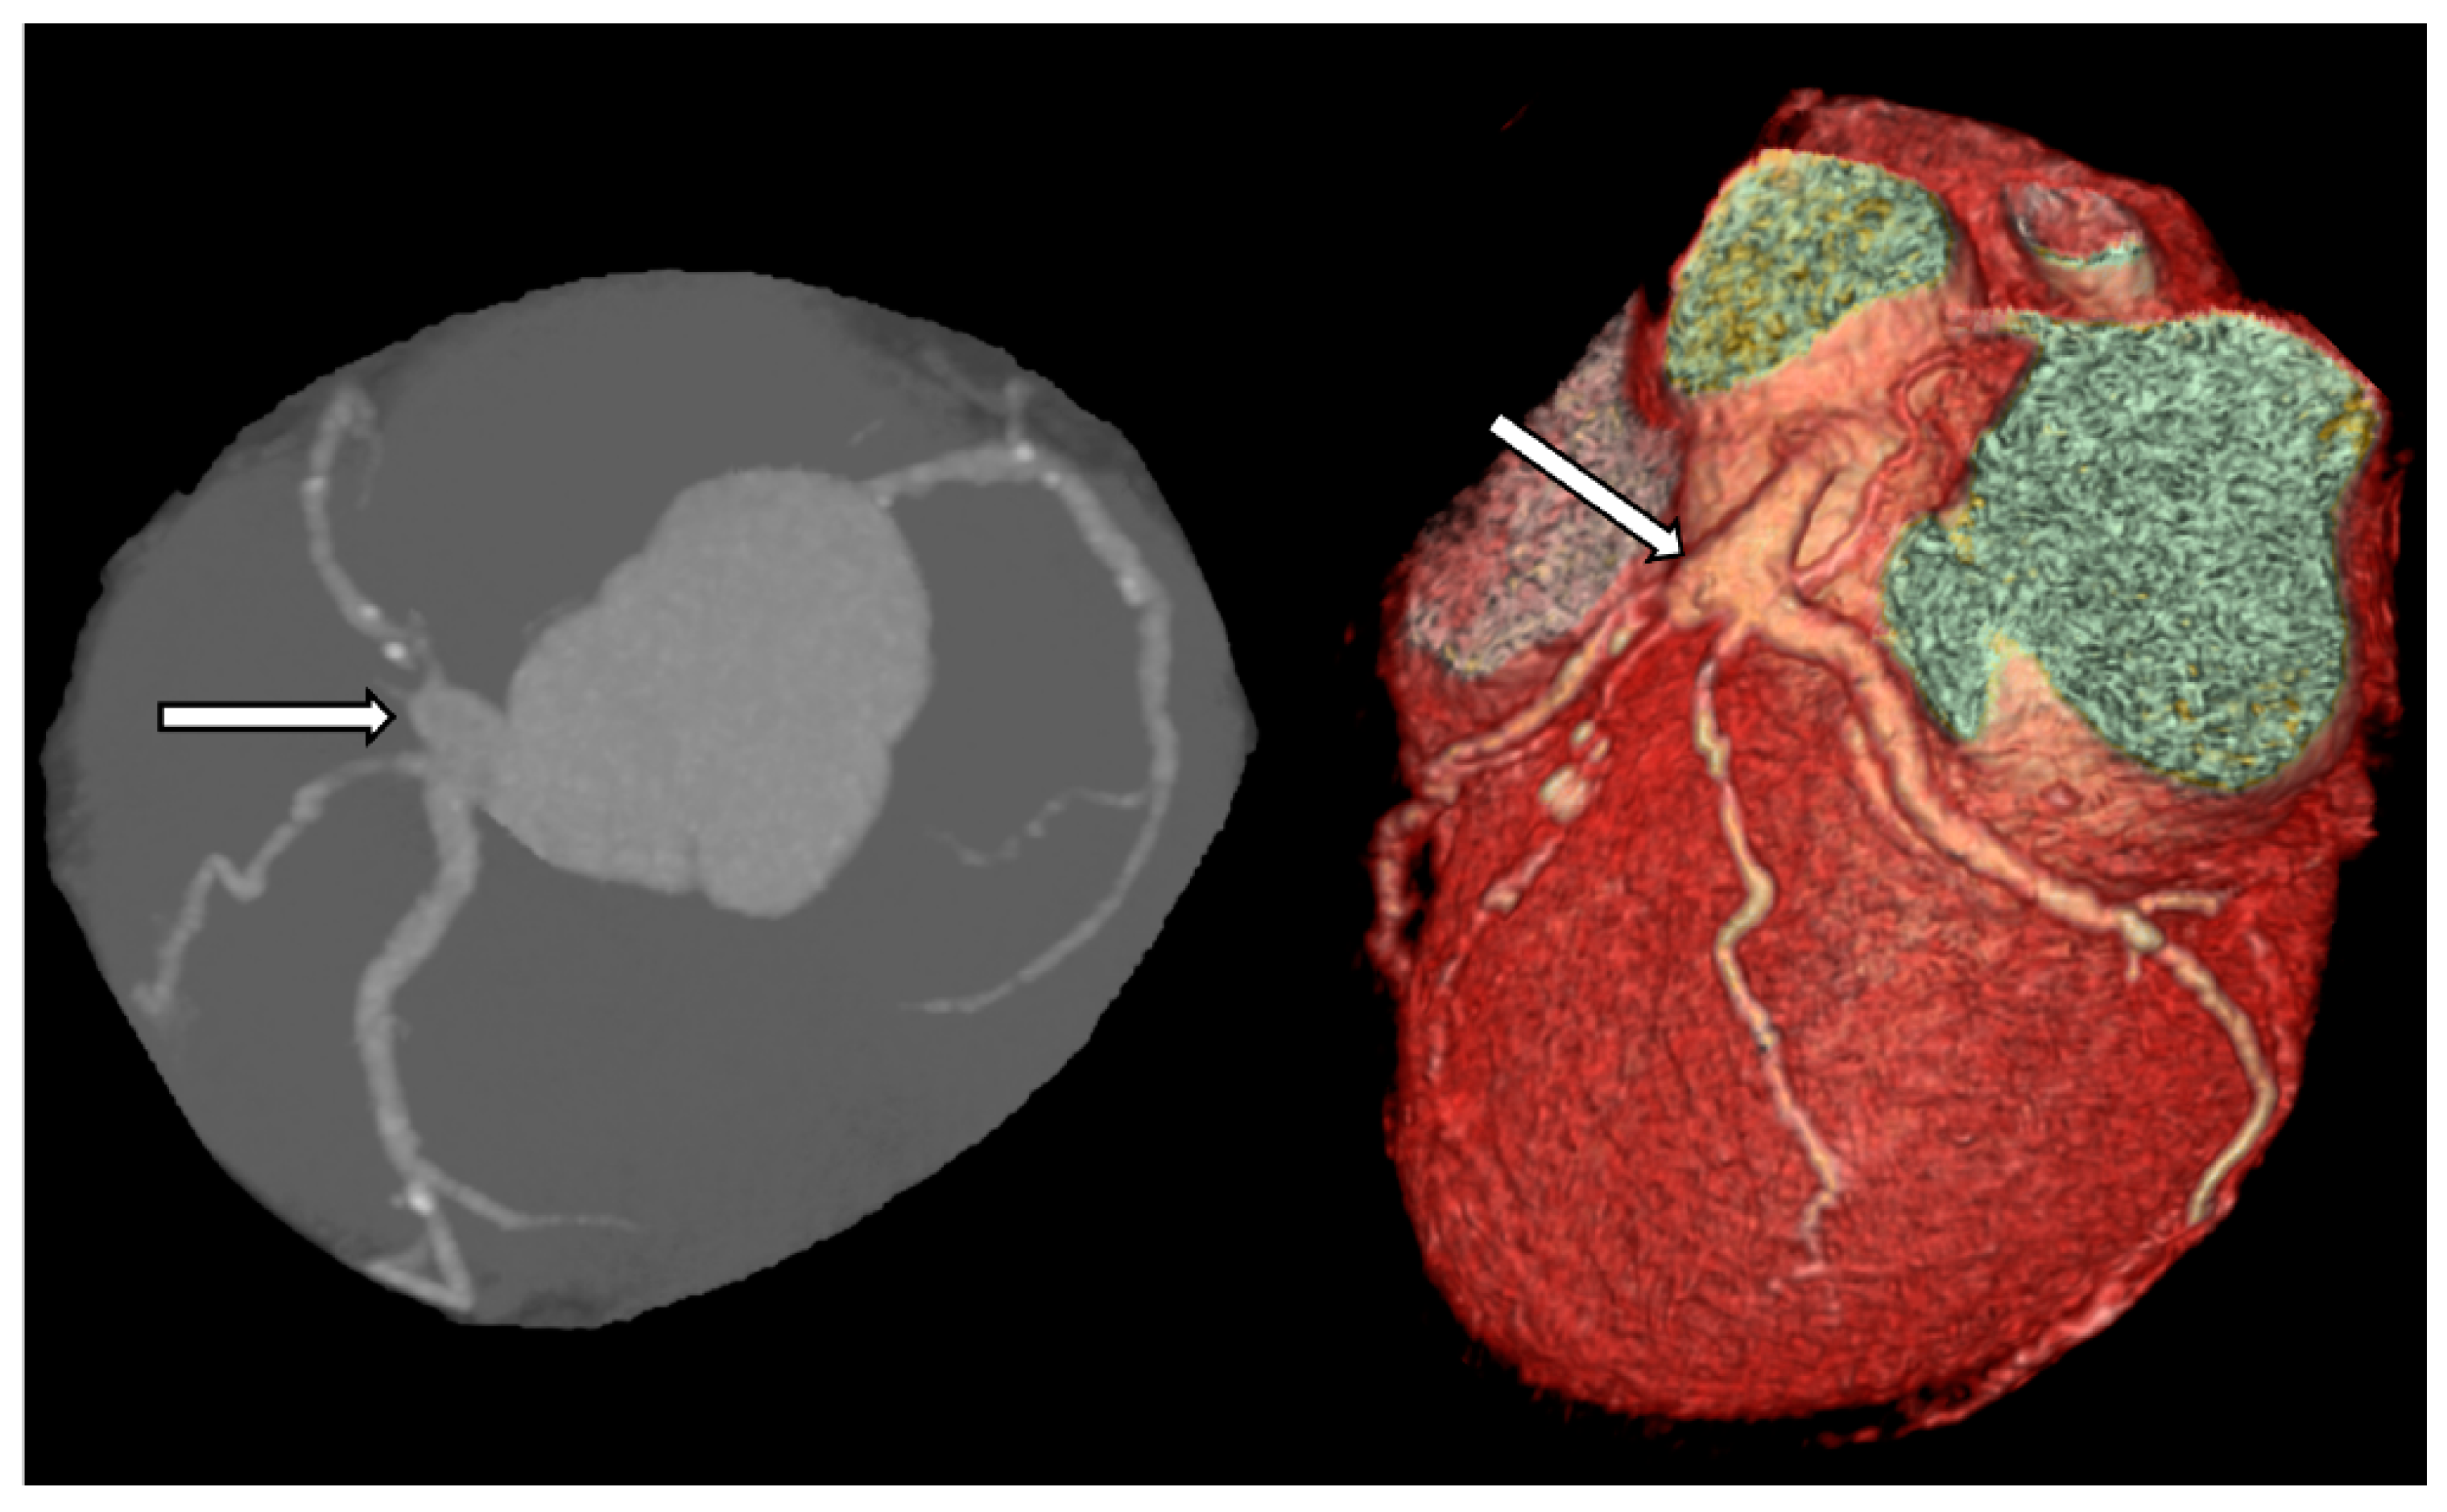

- Murthy, P.A.; Mohammed, T.L.; Read, K.; Gilkeson, R.C.; White, C.S. MDCT of coronary artery aneurysms. AJR Am. J. Roentgenol. 2005, 184 (Suppl. 3), S19–S20. [Google Scholar] [CrossRef]

- Johnson, P.T.; Fishman, E.K. CT Angiography of Coronary Artery Aneurysms: Detection, Definition, Causes, and Treatment. Am. J. Roentgenol. 2010, 195, 928–934. [Google Scholar] [CrossRef]